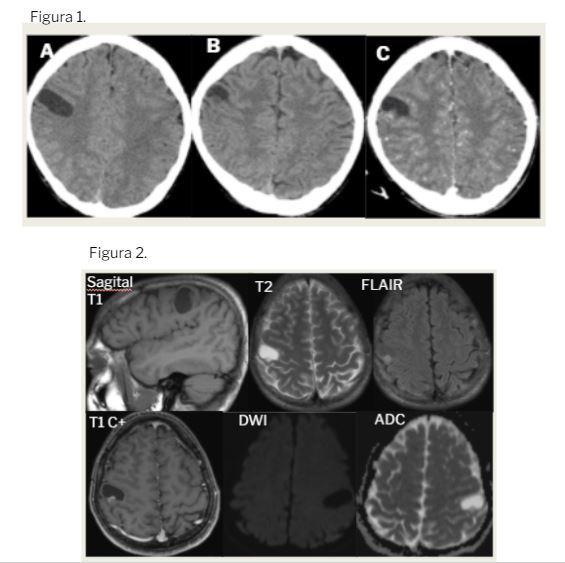

Figura 1: TC secuencial de cráneo sin CIV (A y B) y con CIV (C).

Lesión intraaxial hipodensa bien definida en giro poscentral derecho con pequeño polo sólido intramural isodenso.

Realce heterogéneo de contraste del nódulo sólido intramural. No realce de la pared del quiste.

Figura 2: RM cerebral.

Lesión con componente quístico hipointenso en T1 e hiperintenso en T2 y supresión parcial en FLAIR con nódulo intramural sólido isointenso en T1 e hiperintenso en T2-FLAIR.

T1 con Gd: captación heterogénea del nódulo sólido.

No restricción en secuencias de difusión.